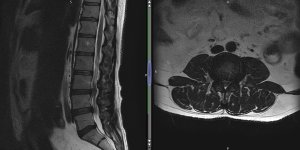

Intestinal Tumour

38 male History of low back pain - approx 5 years. Feb 2021 - attended GP surgery for back pain + left leg pain. Gave a 2 month history for symptoms. Jumped out of a van which made the symptoms worse. Also reported P+N in the left leg. No B+B issues. Booked for FCP appt next day. Patient DNA. July 2021 - attended A&E for GI, Abdominal pain. [...] Read more